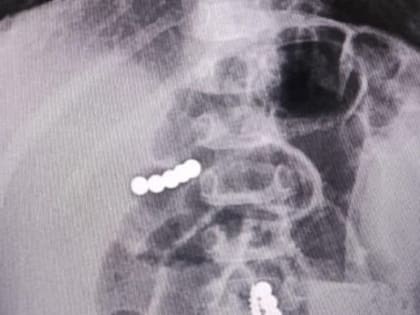

Врачи ставропольской больницы получили патент на новое изобретение

Сотрудники ставропольской больницы скорой медицинской помощи получили патент на новое изобретение для лечения травмы спинного мозга.

Инновационную методику лечения запатентовали нейрохирурги Ставрополя

Специалисты клинической больницы скорой медпомощи Ставрополя получили патент на прорывное изобретение в области лечения травм спинного мозга.